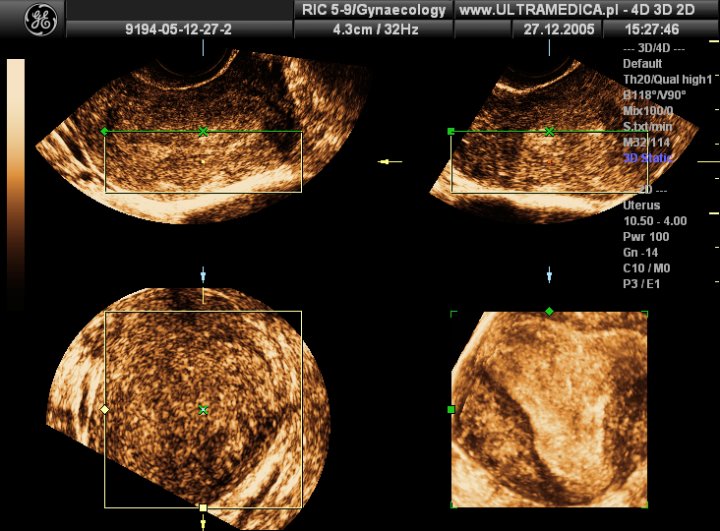

From www.ultramedica.pl

Precyzyjne USG ginekologiczne, dopochwowe, Kraków Ut L Pada Usg Usg transvaginal atau disebut dengan usg endovaginal ini, biasanya direkomendasikan dokter untuk mendeteksi kondisi abnormal pada rahim atau mengecek kesehatan janin. Usg selama kehamilan penting agar anda bisa mengetahui pertumbuhan dan perkembangan janin. Urinary track atau saluran kemih. Limpa, yaitu organ yang berada di perut kiri atas bersebelah dengan lambung. Usg transvaginal (usg tvs) adalah metode pemeriksaan kehamilan serta kondisi. Ut L Pada Usg.